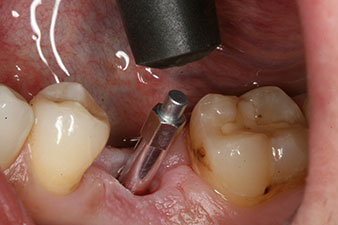

Nach gründlicher Entfernung des Granulationsgewebes wurde das Implantat wie geplant eingebracht (blueSky, bredent).

Das Drehmoment beim maschinellen Einbringen war 43 Ncm. Zusätzlich wurde, nach Einschrauben eines speziellen, auf das Implantatsystem abgestimmten Mess-Pfostens (SmartPeg), der ISQ-Wert mit der Sonde des W&H Osstell ISQ Modul bestimmt.

Dieses Modul ist für das Implantmed von W&H optional erhältlich und wird an den Implantologiemotor gedockt (vgl. Abb. 11). Der dimensionslose ISQ-Wert war direkt bei der Insertion 64 in oro-vestibulärer und 68 in mesio-distaler Richtung (Maximalwert = 100). Dies hätte eine offene Einheilung oder sogar Sofortversorgung erlaubt.